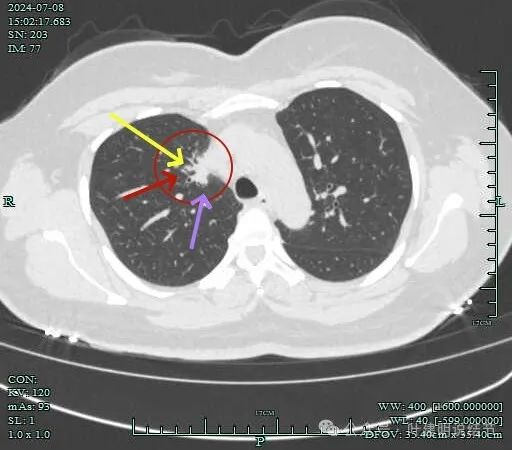

心缘旁另有实性小结节,像良性些。

中叶胸膜下也有小结节,实性。

中叶与下叶胸膜下都有结节。

下叶结节密度较高,边缘有一侧稍模糊。